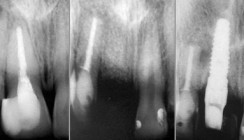

Das interessanteste positive Merkmal war aber ein über die Jahre gleichbleibender röntgenologisch nachvollziehbarer Knochenverlauf (Abb. 8 bis 10).  Durch  entsprechende Modellation konnten wir auch im Seitenzahnbereich die Zirkonoxidanteile flächig auf die Gingiva auflagern, ohne hyperplastische Gingivareaktionen zu erhalten (Abb. 11). Wenn man nun die speziell in der Oberkieferfront erzielten Ergebnisse mit denen vergleicht, die bei zweiteiligen Implantatsystemen mit aufwendiger Flap-Technik  erzielt werden, so kann man kaum mehr Unterschiede zwischen beiden Techniken erkennen (vgl. Abb.  12 und 13).

Der längste ästhetische und physiologisch einwandfreie Erfolg liegt mittlerweile 14 Jahre zurück und liegt in den Anfängen unserer zu dieser Zeit sehr mutigen Modellationstechnik (Abb. 17 und 18). Bei dem Patienten gab es trotz distalen Anhängern in 14 Jahren  nur einen leicht zu reparierenden Facettenbruch bei 21, ansonsten nie  Periimplantitiden oder gar Knochenrückgänge. Relativ typisch für diese Art der Restauration ist eben der gleichbleibende Knochenverlauf, dessen Ursachen sowohl in der Philosophie der einstückigen Implantate begründet liegt, als auch in der Druckverteilung der Kräfte durch die zementierte zirkuläre Brücke.